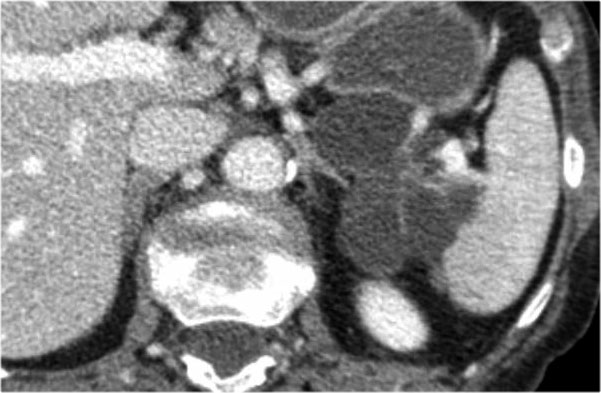

CT cho thấy hai nang lớn ở bệnh nhân nữ 45 tuổi có tiền sử chấn thương (hình).

Lưu ý hình ảnh thâm nhiễm mỡ trong khoang sau phúc mạc (mũi tên).

Kết hợp đặc điểm hình ảnh với tiền sử lâm sàng, rất có khả năng đây là các nang giả tụy do chấn thương.